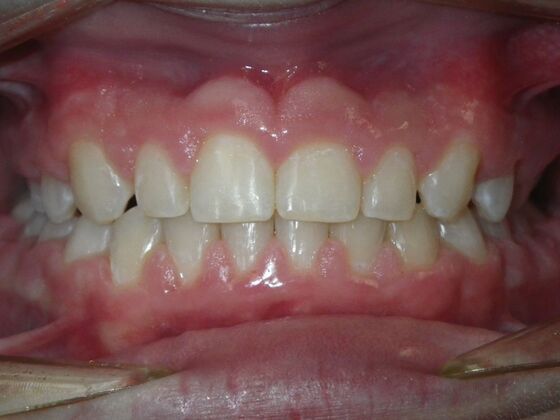

Orthodontic treatment in Phases: Case 8

Description

Dylan presented with a functional crossbite in which we used removable expansion appliances for 12 months, followed by bracketing of upper and lower teeth including primary ones to gain alittle more expansion, allowed to wear retainers for 6 months and then followed closely with 6 month ortho recalls and began Phase 2 treatment within 24 months and finished his ortho treatment.